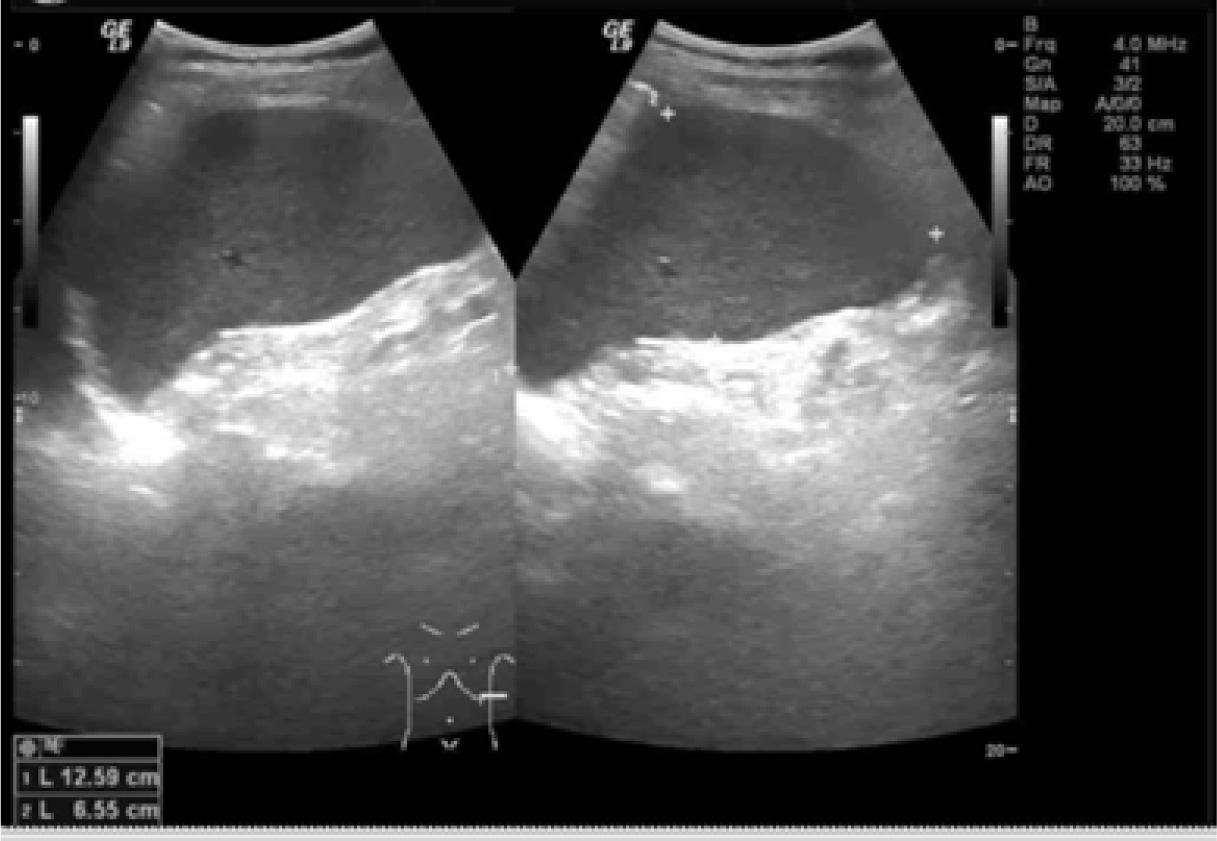

Figure 1